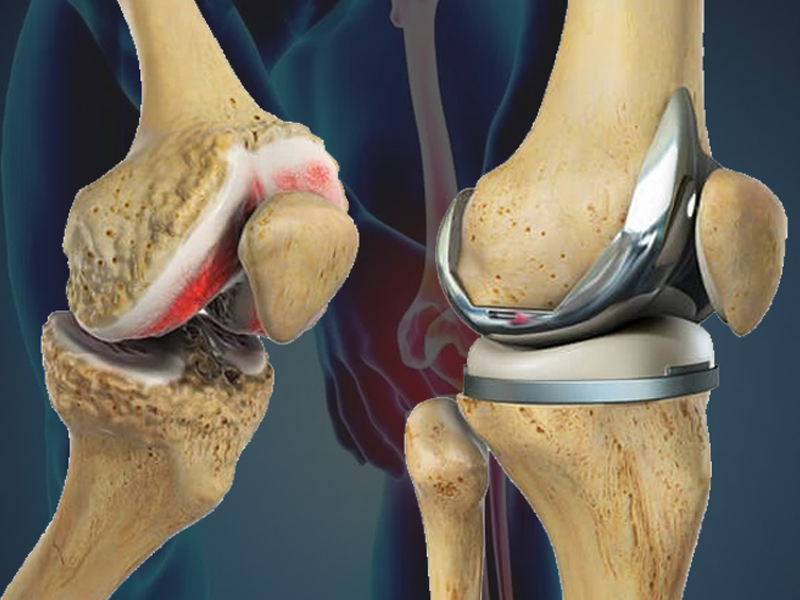

Knee Replacement

Knee replacement surgery replaces parts of injured or worn-out knee joints. The surgery can help ease pain and make...